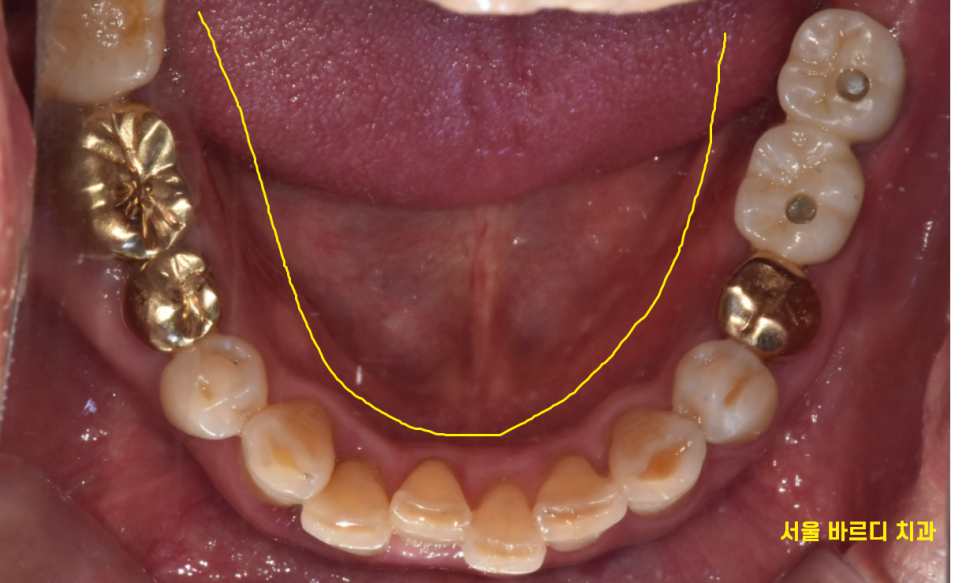

구강은 네모 반듯하지 않죠?

라운드입니다.

곡선을 직선으로 옮기다 보니 한계가 있습니다.

2차원 사진의 왜곡도 있을 수 있고

(겹쳐지는 부분이나 앞니는 잘 안나옵니다)

240610

3차원적 관계를 ct를 통해 확인이 가능합니다.

앞, 뒤, 좌, 우, 옆

360도 돌려가며 파악이 가능합니다.